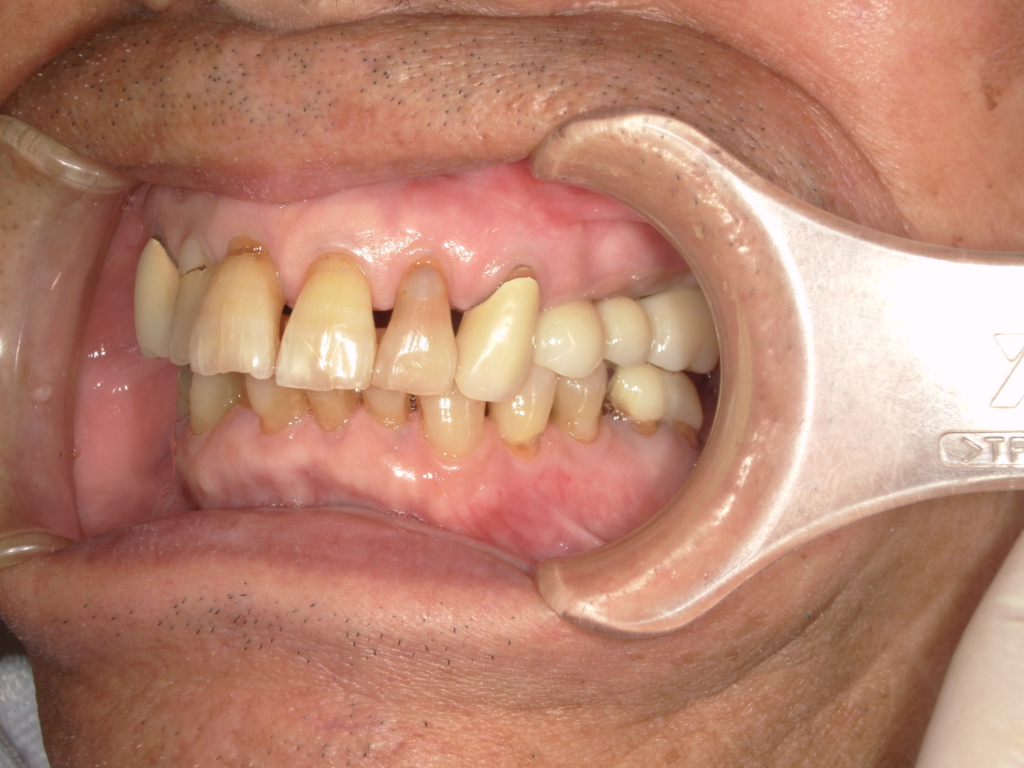

Y様インプラント実例 #44

左の上下の奥歯をインプラントで治療しています。

左下の奥歯は歯を抜くのと同時にインプラントの埋め込みを行っています。

被せものは上下、セラミックスで作っています。

治療前

治療後